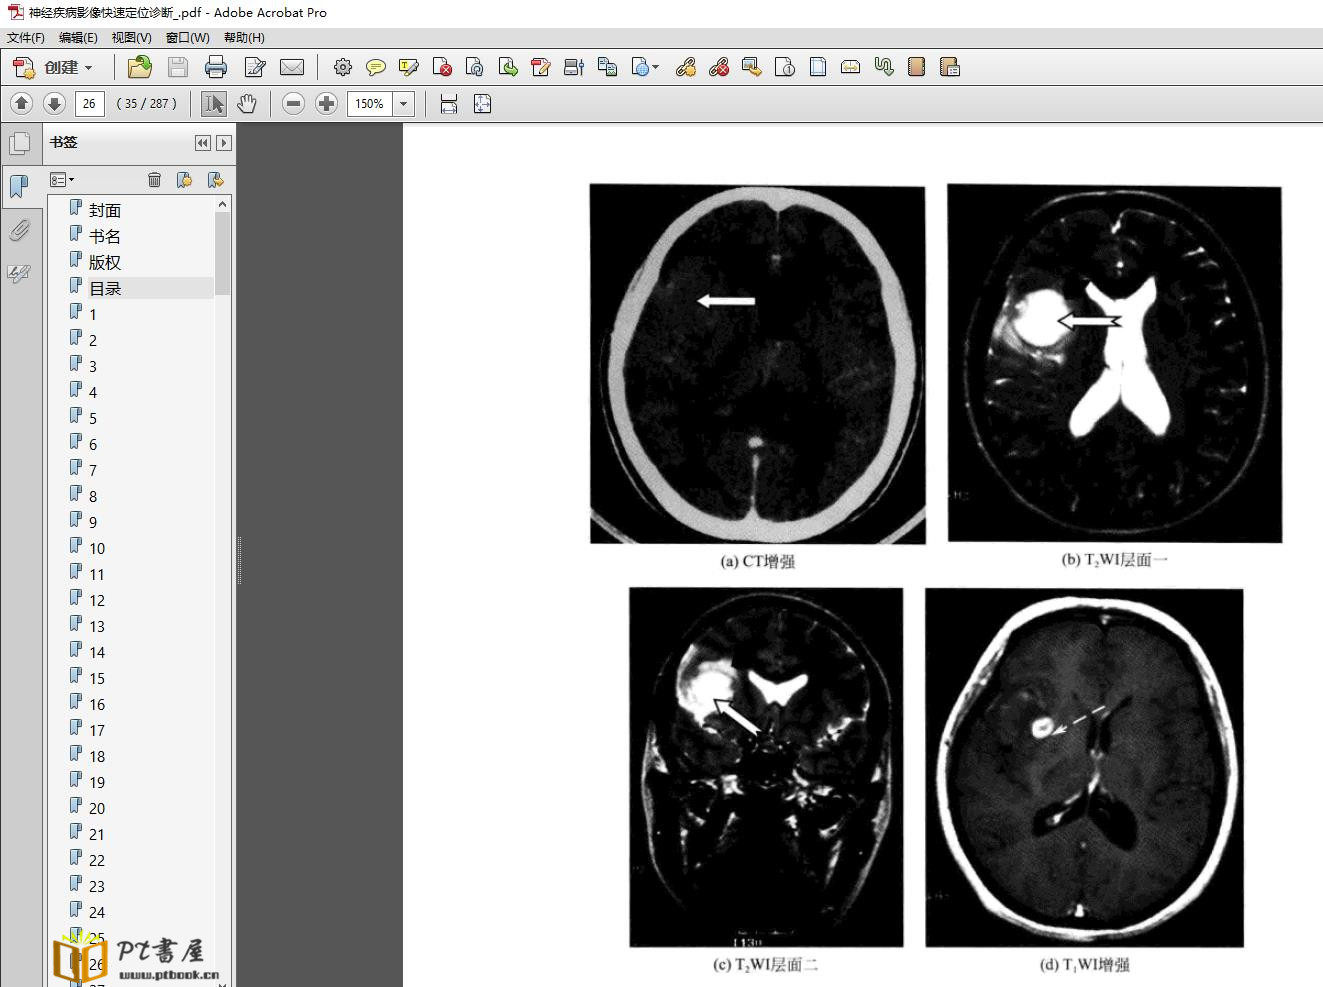

本书按照发病部位分六章介绍了神经系统常见病的影像定位诊断。每个病种都从临床背景、影像定位诊断、常见误区与注意事项三个方面阐述,并配以典型的影像图片,使读者直观、清晰地掌握定位诊断思路和方法。